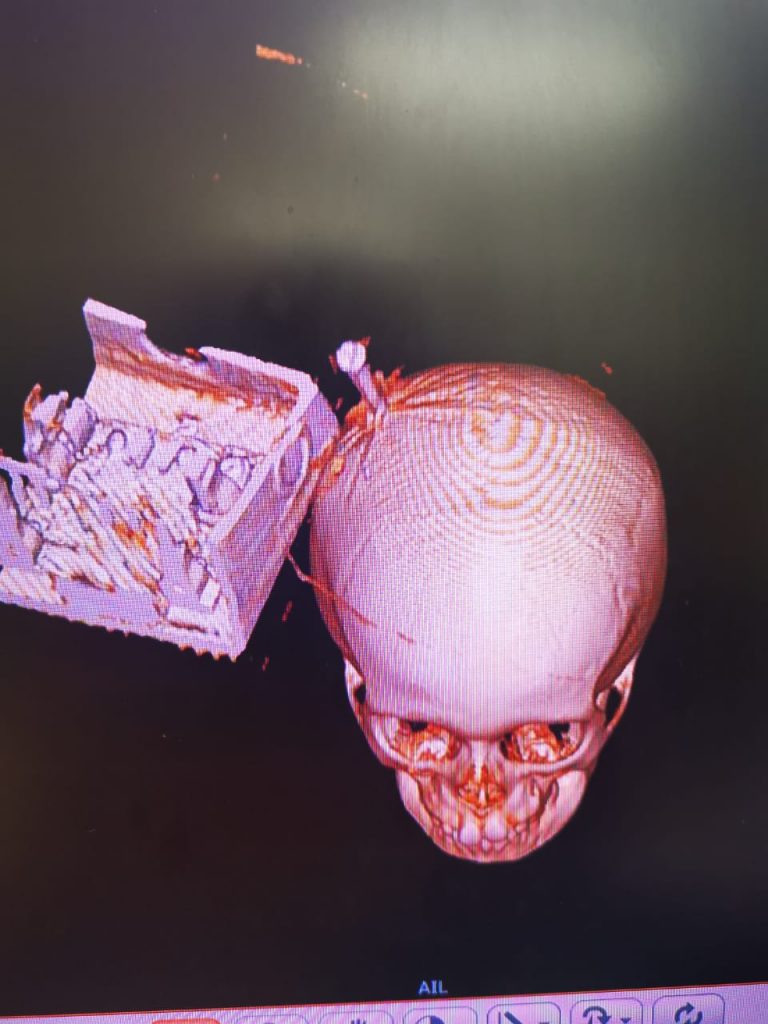

Gilberto llegó ese mismo día al hospital. Tras realizarle diversos estudios, el diagnóstico fue “herida penetrante de cráneo por cuerpo extraño punzocortante”, por lo que antes de que pudiera ser intervenido quirúrgicamente fue necesaria una vez más la participación de los paramédicos ecatepenses y de personal de la Cruz Roja, para reducir el tamaño del objeto que tenía en la cabeza, es decir, retirar el switch y cortar la tabla.

Para sacar el objeto del cráneo del menor, que entonces sabían con certeza se trataba de un tornillo, fue necesario realizarle una craniectomía, una intervención quirúrgica que requirió desprender una pequeña parte del cráneo del menor para que la pieza metálica pudiera ser retirada sin riesgos colaterales.